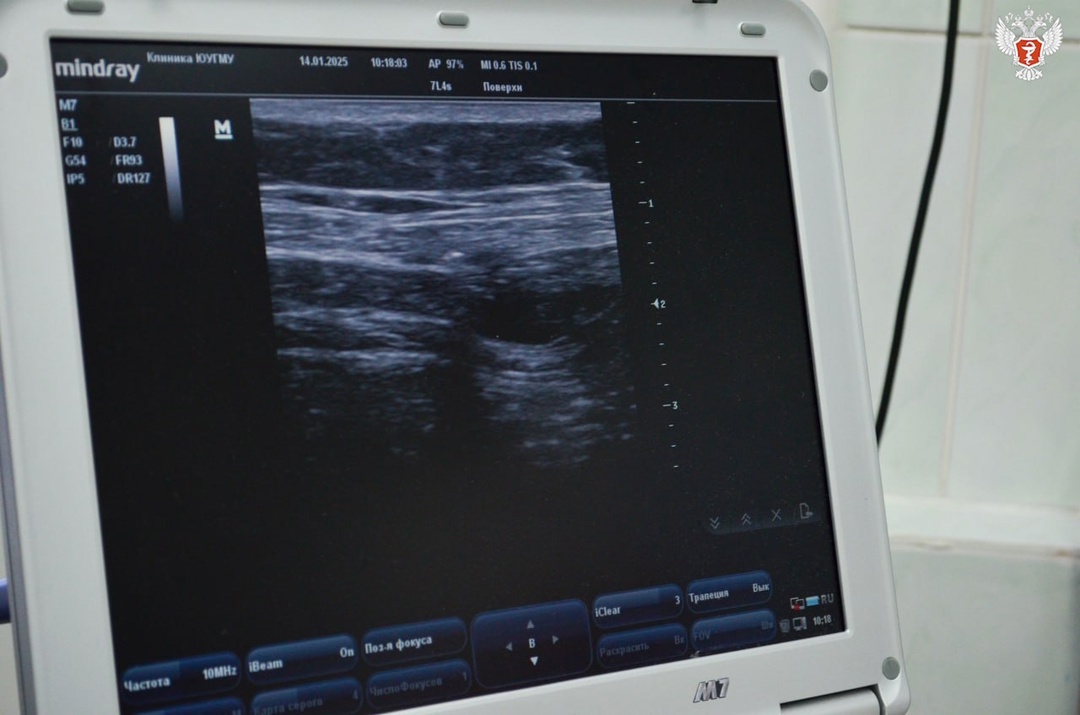

Для эффективности данного вида обезболивания анестезиологи-реаниматологи применяют УЗИ-навигацию, что значительно снижает возможные риски и практически исключает осложнения.